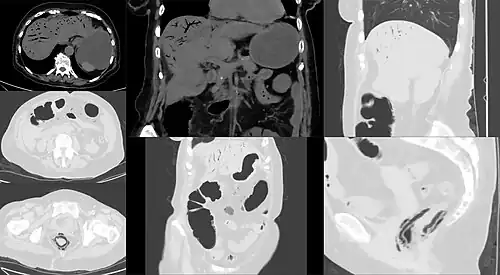

CT image showing mesenteric ischemia with pneumatosis intestinalis and gas in mesenterial and liver veins

Computed tomography (CT scan) is often used.[29][30] The accuracy of the CT scan depends on whether a small bowel obstruction (SBO) is present.[31]